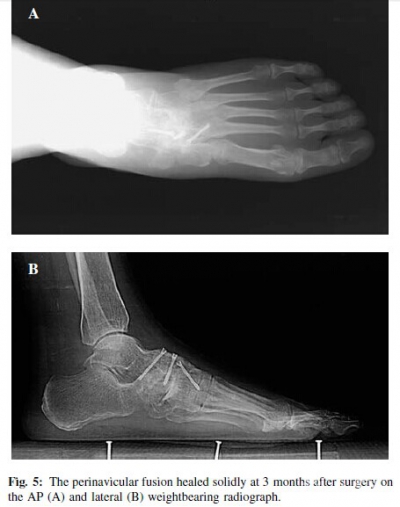

At the last followup, all feet were pain·free, and the deformity was also corrected satisfactorily without any surgical complication including infection, skin necrosis, and nerve injury. There was no case of persistent graft donor site pain at the hip. The average AOFAS ankle·hindfoot score was improved from 40.1±8.3 preoperatively to 90.9±2.1 at the last followup (p = 0.0004).Radiographically, all the feet fused solidly at 3 months after surgery without screw breakage or loosening (Figure 5).The foot appearance improved with normal longitudinal arch height on the lateral view (Figure 6). The average longitudinal arch height increased from 46.1± 2.1mm preoperatively to 53.5±2.3 mm at the last followup (p < 0.05) on the lateral weightbearing radiograph.

The perinavicular arthrodesis can be performed through a medial or dorsal approach. The dorsal approach, used in this group of patients, allowed easy exposure of the navicular, cuneiforms, and head of the talus while avoiding neurovascular structures. According to Watson·Jones,a trapezoidal bed can be carved on the navicular from the talus to the cuneiforms. A tricortical autogenous graft of this shape was obtained from the iliac crest and inserted in the bed with the aid of plantarflexion of the foot. Meanwhile,if the steps were performed carefully, as Watson-Jones described, osteosynthesis devices were unnecessary because the graft entered in a self-locking receptor bed. However,we felt it was not a stable fixation for arthrodesis.In this group, we used a rectangle bed (more easily carved than the trapezoidal bed as well as a tricortical autogenous graft. In addition, to prevent potential non·union, three cannulated titanium 4.0mm screws were implanted through the tricortical autogenous. Postoperatively, all the feet fused solidly at 3 months after surgery without screw breakage or looseness.